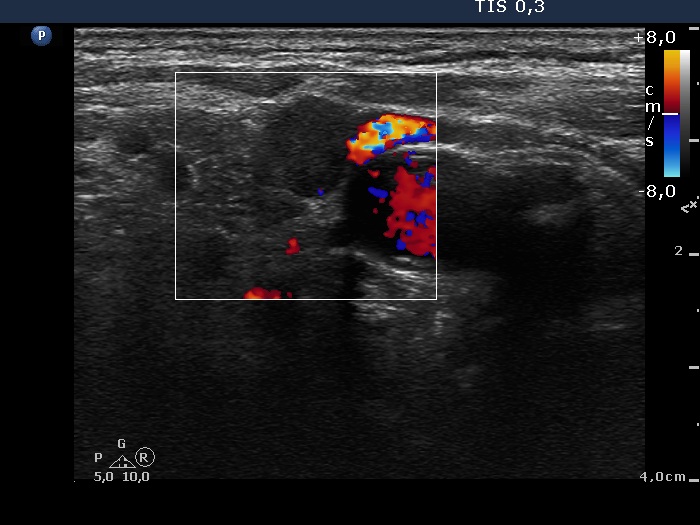

Lateral to the right thyroid, transverse scan, color Doppler mode. The node presents a type 1 vascular pattern.